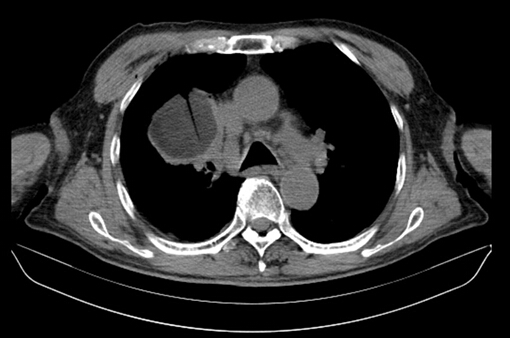

1、 氬氦刀靶區(qū)成像邊界即是消融邊界,不會(huì)產(chǎn)生偽影,可達(dá)到“所見即所得”的最佳。為臨床治療提供準(zhǔn)確影像依據(jù),可避免治療不足造成腫瘤殘留,或過度治療造成相鄰組織損傷。在CT圖像中,由于組織結(jié)冰后體積增大,靶區(qū)密度降低,冰球圖像下降40-50HU,形成清晰的陰影區(qū)。在B超成像中,冰是弱回聲的(暗區(qū)),冰球邊緣呈強(qiáng)回聲區(qū)(亮帶)。

治療后